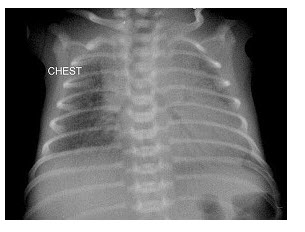

80、单项选择题

早产儿,男,生后12小时,生后8小时出现呼吸困难,如图,最可能的诊断为()

A.新生儿肺炎

B.新生儿湿肺

C.新生儿肺出血

D.新生儿特发性呼吸窘迫综合症

E.胎粪吸入综合征